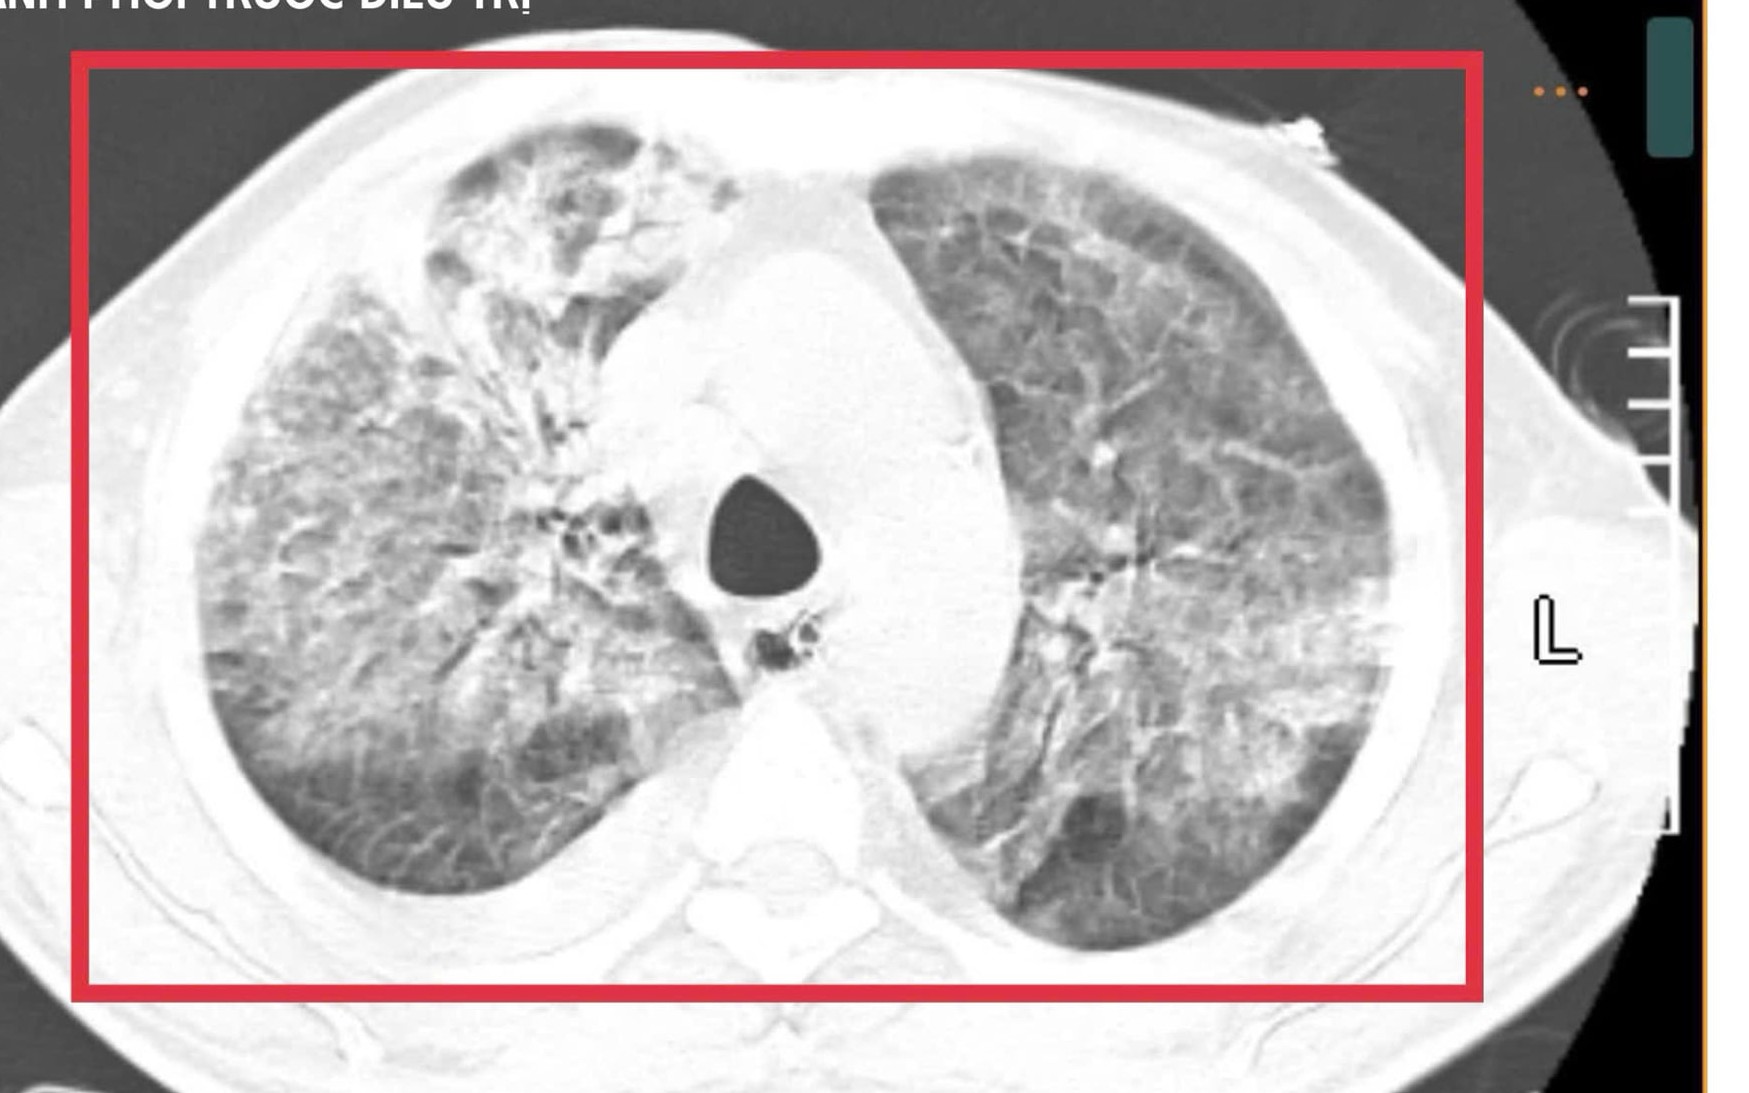

Hình ảnh bệnh nhân Whitmore từng điều trị tại Bệnh viện Bệnh Nhiệt đới TPHCM

Whitmore có biểu hiện đa dạng, dễ nhầm lẫn với nhiều bệnh khác. Người bệnh có thể bị sốt cao, viêm phổi, áp xe ở da hoặc nhiều cơ quan như gan, lách, thận. Một số trường hợp xuất hiện các vết loét, hoại tử trên da khiến bệnh bị gọi nhầm là "vi khuẩn ăn thịt người", gây hoang mang dư luận. Thực tế, đây là bệnh nhiễm trùng nặng chứ không phải vi khuẩn "ăn thịt" theo nghĩa đen.